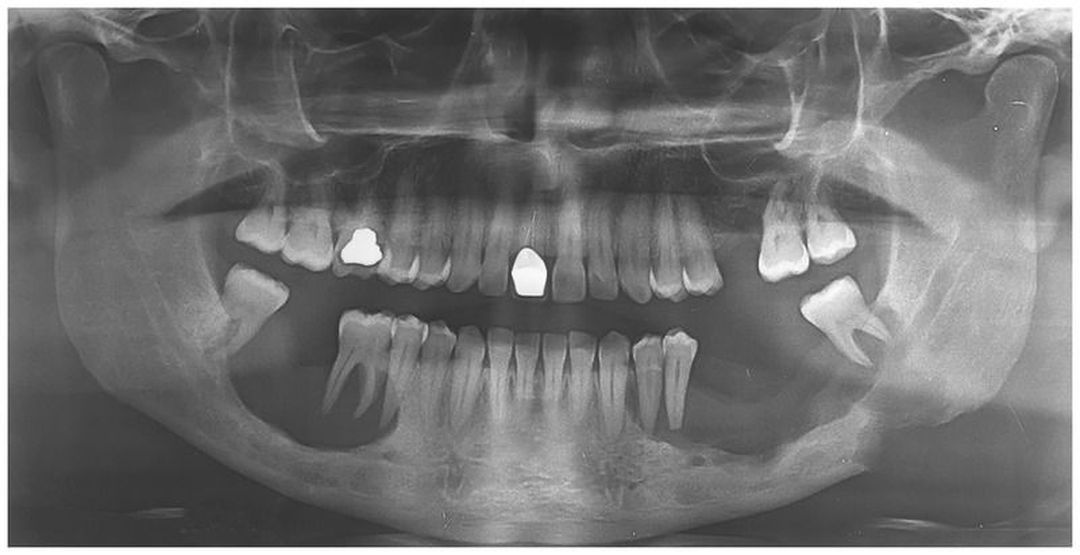

A 36-year-old man presented with a 1-year history of oral pain and loose teeth; four teeth had been lost spontaneously within the 6 months before presentation. Increased thirst and urination also developed within 4 months before presentation. Blood electrolyte levels revealed hypernatremia and dehydration. A panoramic radiograph showed two radiolucent scooped-out lesions of the mandible with “floating tooth” images. Biopsy of the mandibular lesion on the left side revealed sheets of inflammatory-cell proliferation and S100+ CD1a+ Langerhans’ cells. Magnetic resonance imaging of the brain revealed an increased T1-weighted signal in the posterior pituitary and thickening of the infundibulum Multiorgan Langerhans’-cell histiocytosis with diabetes insipidus was diagnosed. Langerhans’-cell histiocytosis is a clonal proliferation of Langerhans’ cells. Oral lesions are estimated to occur in 10 to 15% of patients. This patient was treated with curettage and desmopressin. The patient had no recurrence 6 months after surgery.